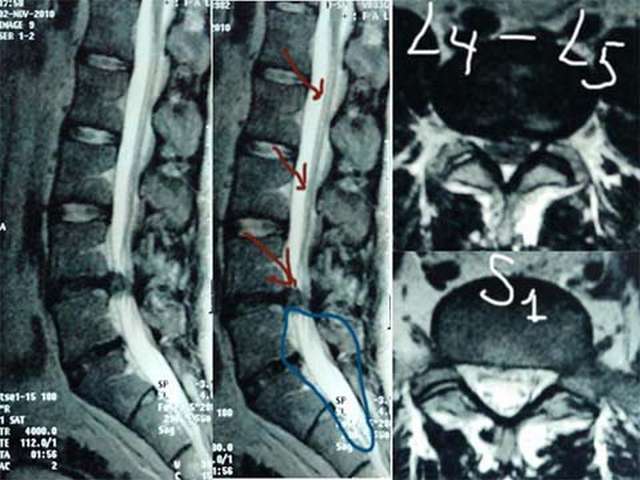

Мужчина 30 лет 3 месяца назад впервые ощутил резкие боли в области поясницы с иррадиацией в правую ногу. Неврологическое обследование выявило негрубую радикулопатию корешка L5 справа. Принимал нимесулид и мидокалм, занимался лечебной гимнастикой по специальной программе – без эффекта. Дважды выполнялась селективная корешковая блокада L5 справа – без эффекта. Выполнена МРТ поясничного отдела позвоночника: выявлена парамедианная грыжа диска L4-L5 0,9х0,4 см. Кроме того, специалистами МРТ выявлены признаки врожденного синдрома натянутого спинного мозга (tethered cord syndrome): спинной мозг прослеживается до уровня S2 позвонка и заканчивается в липоме, окружающей концевую нить на уровне S3, дистальные отделы дурального мешка расширены, конус спинного мозга имеет атипичную вытянутую форму. При дополнительном целенаправленном опросе было установлено, что пациент рос и развивался нормально, активно занимался споротом, участвовал в соревнованиях и до 30 летнего возраста болей в позвоночнике не испытывал. Недержания мочи и кала никогда не отмечал. Чувствительность в области промежности не нарушена. Тонус анального сфинктера нормальный. Анальный рефлекс сохранен. Вопросы: действительно ли мы имеем местно с врожденным синдромом натянутого спинного мозга, который выявлен случайно после появления грыжи диска? Хирургическое лечение следует ограничить микрохирургической дискэктомией или необходимо дополнительно рассечение концевой нити с удалением липомы?

Честно говоря, на представленных МР томограммах я не вижу признаков СНСМ. Но описание прилагается, с подписью и печатью.